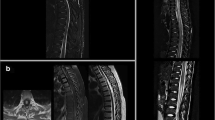

a–c Example of an MS-related myelitis in a 28-year-old patient. a Circumscribed, round T2-hyperintense lesion at the level C4 (arrow). b focal contrast enhancement (arrow). c Asymmetric and eccentric location on axial T2-w images. d–g LETM in a 76-year old patient with AQP4-positive NMOSD. d Diffuse longitudinal T2- hyperintensity and swelling of the SC between C4 and T5 accentuated at the levels T3-5. e The axial view of the SC at the intervertebral disc level T3/T4 shows central cord involvement with (f) contrast enhancement. g Six months follow-up MRI with signs of pronounced SC atrophy, most prominent at the levels T2–4 (arrow). h–j Example of a 66-year old woman with AQP4-positive NMOSD in the context of Sjögren’s syndrome and SLE. h Irregularly shaped longitudinal T2-hyperintense lesions in the thoracic cord with i and j. bright spotty lesions on axial T2-w images. k–n Example of a sarcoidosis-associated myelitis in a 48-year-old patient with longitudinally extensive SC lesions. l, k Longitudinally extensive lesions in the medulla, cervical and thoracic SC with subependymal contrast enhancement (k, arrows). m, n. dorsal subependymal gadolinium enhancement and enhancement of the central canal (n, arrow)

Multiple sclerosis (MS) is the most common immune-mediated disorder of the central nervous system (CNS) with a progressive evolution of demyelinating lesions and atrophy. Severe clinical symptoms, e.g. restricted ambulation and bladder dysfunction, result mainly from SC involvement. More than 80% of patients with newly diagnosed MS show T2-hyperintense SC lesions on sagittal MRI. SC lesions due to demyelination can usually be differentiated from those that are related to other inflammatory disorders or vascular disease, since meningeal involvement, vertically spreading lesions over several segments and horizontally spreading lesions involving a significant part of the SC are atypical for MS [6]. MS lesions are typically short (less than 3 vertebral segments), multifocal and primarily located in the cervical cord (Fig. 1a–c) [7, 8]. However, involvement of the thoracolumbar region can be seen in up to 40% of cases [6, 8, 9]. MS-related SC lesions are mostly located in the dorsal or lateral columns, present rather asymmetrically and do not respect the gray and white matter boundaries [10]. Recommendations of the magnetic resonance imaging in MS (MAGNIMS) Consortium suggest to perform two sets of sagittal images with different contrasts (e.g. dual-echo T2/Proton density or short tau inversion recovery) of the whole cord at a minimum field strength of 1.5 T as part of the diagnostic work-up [2]. An additional axial plane should be added to increase diagnostic certainty when T2-hyperintensities in the sagittal plane are inconclusive [2, 8, 9]. In particular, diffuse hyperintensities, a common feature in patients with primary progressive disease type, are well depicted in the center of the cord cross-section [8, 11, 12]. Ring-like gadolinium enhancement may be present in lesions; however, gadolinium enhancement is also often associated with clinical MS symptoms and cord swelling [13]. Therefore, the application of contrast media in disease monitoring of MS cord changes is a matter of debate. Yet, in the work-up of differential diagnoses (see below) a 2D or 3D T1-weighted (T1-w) scan after contrast media is still mandatory [2, 14]. For a long time, the frequency of focal T1-hypointensities in the SC of MS patients has been underestimated [15]. However, higher field strength and better resolution of 3D images now enable improved detection of chronic T1-hypointense lesions within the cervical cord particularly in patients with progressive MS, with moderate correlation between T1-hypointense lesion count and disability [5]. MRI of the SC shows prognostic value in MS as well. While the presence of SC lesions may be associated with a worse prognosis in relapsing-remitting MS (RRMS) [16,17,18], in radiologically or clinically isolated syndromes the presence of cord lesions predicts the conversion into definite MS [19,20,21]. Nevertheless, the correlation between focal cord demyelination and disability is weak. A more promising biomarker could be SC atrophy that can be easily assessed on conventional 3D T1-w scans. SC atrophy can be detected in all stages of the disease [22]. In patients with RRMS, SC volume loss correlates with the number of relapses [23]. In progressive cases the evaluation of SC atrophy seems to be especially meaningful [24,25,26] with smaller upper cervical cord area (UCCA) and faster atrophy rates in progressive versus relapse-onset patients. Moreover, in patients with progressive MS the extent of atrophy correlates with clinical impairment and acts as an independent predictor of disease progression [25,26,27]. Conventional MRI unfortunately only allows for the quantification of overall SC volume or cross-sectional area [28,29,30,31]. Novel, advanced magnetic imaging techniques, such as phase-sensitive inversion recovery (PSIR) imaging [32] and averaged magnetization inversion recovery acquisition (AMIRA) imaging [33] now allow for improved contrast between gray and white matter in the SC. Application of the former revealed cervical SC gray matter atrophy in MS patients even if signs of white matter atrophy were missing. SC gray matter atrophy correlates well with clinical disability and disease course [34, 35]. Furthermore, quantitative MRI techniques including the measurement of the myelin water fraction and the myelin thickness may give additional information about the disease severity and progression [36, 37]. While SC imaging in MS is currently used for diagnostic work-up at disease onset [2], the value of monitoring disease using it at regular intervals is still debated [38, 39]. In particular, measurements of SC atrophy have the potential to be part of future clinical care and monitoring of disease progression [23].

One of the classical manifestations of the disease is longitudinal extensive transverse myelitis (LETM), with high risk of recurrence in patients with AQP4-IgG antibodies [49, 50]. In contrast to MS, NMOSD lesions extend over three or more vertebral segments (Fig. 1 D) [42, 51]. Takahashi et al. reported a positive correlation between the length of the SC lesion and the serum level of AQP4-antibodies [52]. The length of the lesion visible on MRI crucially depends on the timing of the imaging study. Short segment myelitis has been described to be present in 14% of antibody-positive patients early in the course of LETM [53] or during recovery. After treatment with steroids, LETM has been shown to change in morphology with the appearance of several shorter lesions in about a quarter of patients [54].

NMOSD SC lesions are predominantly located in the cervical cord, with frequent extension into the thoracic cord or into the brainstem. About 30% of patients show thoracic cord lesions [54]. 60–70% of SC lesions observed in NMOSD occupy more than half of the cord area (Fig. 1e, f). Given the high expression of AQP4 around the central canal and in SC gray matter, lesions predominantly involve the central gray matter [55] (Fig. 1e, f), but frequently extend to the pial surface on axial images [56]. Bright spotty lesions on axial T2-w images are a relatively specific finding in NMOSD [57, 58], and help differentiating NMOSD from MS (Fig. 1i, j). Central hypointensities on T1-w images, cord expansion due to swelling, and gadolinium enhancement are also frequently observed in NMOSD [58, 59]. Ring-like enhancement of lesions (as frequently observed in MS) can be seen in about 30% of patients with NMOSD myelitis [60] and therefore, does not allow for the differentiation between these disorders. In contrast to MS, asymptomatic SC lesions are only rarely reported in NMOSD with a frequency suspected to be less than 5% [61, 62].

Focal or generalized atrophy is seen in up to 50–60% of NMOSD patients with history of myelitis on follow-up MRI [54, 59] (Fig. 1g) and is of high relevance, as SC atrophy correlates well with disability and number of relapses [63]. SC atrophy is even reported in patients with AQP4-IgG positive NMOSD without prior myelitis or SC lesions [64].

Sjögren’s syndrome (SS) is a systemic autoimmune-mediated disorder that primarily affects the salivary and lacrimal glands through mononuclear infiltration and destruction, causing the typical sicca symptoms. SC involvement is reported in 20–35% of SS patients and may present as acute myelitis or chronic progressing myelopathy [108,109,110]. In about 36% of cases with initial neurological manifestations, myelitis was the presenting symptom [110]. Lesions are typically longitudinally extensive and are located in the cervical cord. Some patients additionally present with optic neuritis and/or cerebral lesions and fulfil the diagnostic criteria of concomitant MS [110]. Similarly to SLE, the association of SS and NMOSD has been reported in various publications: the clinical diagnosis of SS may coexist with NMOSD clinical syndromes in AQP4-IgG positive patients (Fig. 1h–j) [89, 111,112,113].

Sarcoidosis-associated myelitis often presents as a LETM that can affect both the cervical and thoracic cord in isolation or as panmyelitis [119, 120]. The typical MRI finding of sarcoidosis-associated myelitis is a longitudinal extensive T2-hyperintense lesion, most commonly located in the dorsal and centrodorsal cord (Fig. 1l). Dorsal subpial enhancement [121] (Fig. 1k) in combination with central canal enhancement (Fig. 1n) can result in a “trident sign” on axial images [122] (Fig. 1m) and can help distinguishing sarcoidosis myelitis lesions from NMOSD lesions [123]. Moreover, an anterior and posterior leptomeningeal enhancement pattern has been described [124]. Spreading to the Virchow–Robin spaces results in parenchymal involvement, which appears as diffuse cord enlargement in MRI [125].